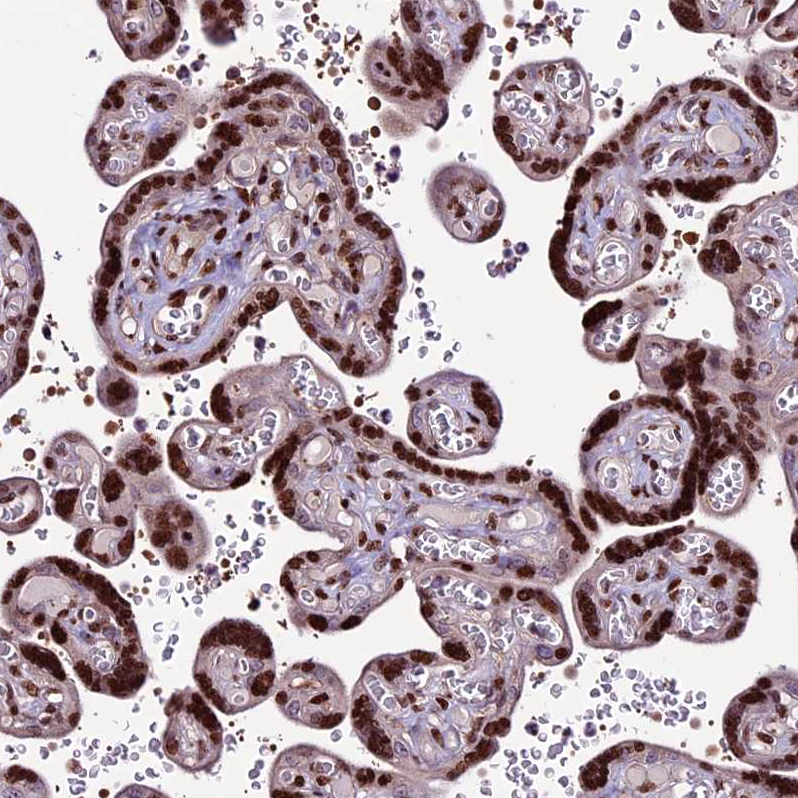

Immunohistochemical staining of human tonsil shows strong nuclear positivity in non-germinal center cells.